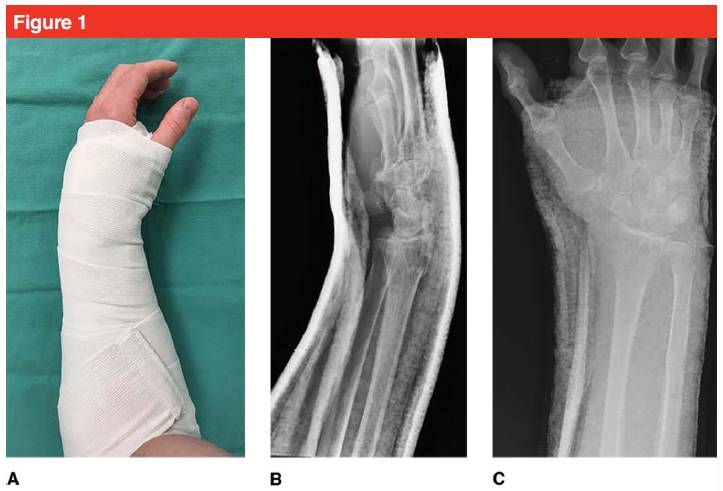

Dans notre centre, les fractures du radius distal peu déplacées sont généralement immobilisées avec une attelle en plâtre en forme de pince à sucre sur le coude pour limiter la pronation et la supination du coude (voir Figure 1).Si le déplacement de la fracture est important, une attelle en pince à sucre doit être réalisée après réduction fermée.Notez que lors de l'immobilisation d'une attelle en plâtre, la portée de l'immobilisation doit s'arrêter à l'extrémité proximale du doigt, afin de faciliter le mouvement du doigt et d'éviter la raideur.L'utilisation de bandages élastiques pour une fixation par compression limitée peut aider à l'attelle.Le type de fracture détermine la méthode de réduction fermée.Si nécessaire, une anesthésie locale par hématome du radius distal peut être choisie, puis une réduction de la traction est effectuée en tirant les doigts (index et majeur) pour corriger la déformation et rétablir l'alignement de l'articulation radiocarpienne.La réduction de la traction est généralement réalisée en utilisant le mécanisme de fracture inverse.La réduction de la traction dans différents plans est nécessaire pour compléter la restauration ligamentaire et rétablir l'alignement des fragments de fracture, du capitule et du lunatum.Sur le plan coronal, restaurer l'alignement anatomique du cubitus et du radius, du fragment osseux distal et de la diaphyse radiale.La réduction d'une fracture de Colles typique nécessite que l'assistant tienne le pouce du patient dans une main et les 4 doigts du patient dans l'autre main, en appliquant une contre-traction pour séparer le fragment de fracture de la métaphyse du radius, en continuant la traction longitudinale, puis palmaire.Flexion et déviation ulnaire pour aider à réduire le fragment de fracture.Pour les patients âgés présentant des lésions des tissus mous environnants, une manipulation soigneuse est nécessaire pendant le processus de réduction pour éviter les déchirures cutanées (un coton peut être utilisé pendant la réduction).Après repositionnement, un examen neurovasculaire a été réalisé.

Figure 1. (A) Un patient avec une fracture du radius distal a été immobilisé dans une position palmaire légèrement neutre avec une attelle en plâtre Sugar Tong pour éviter tout nouveau déplacement ;(B) et (C) radiographies de face et de profil montrant une bonne fixation du poignet du patient.L'attelle plâtrée ne dépasse pas la tête métacarpienne afin que les doigts puissent bouger normalement.